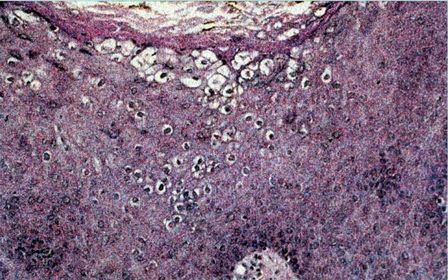

Diagnóstico ECZEMA AGUDO

Diagnóstico ECZEMA CRÔNICO